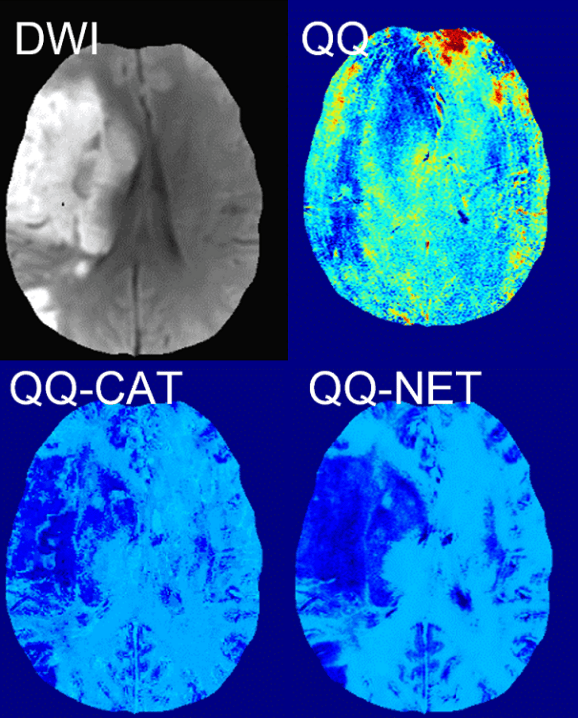

To solve biophysics models robustly, we are developing data processing algorithms including machine learning and deep learning approaches. The biophysics models are complicated with having coupled, multiple model parameters. Hence, they are difficult to solve, e.g., involved with poorly conditioned non-convex optimization. To obtain reliable OEF, machine learning and deep learning algorithms have been developed. For instance, cluster analysis of time evolution (CAT) is a machine learning algorithm that improves effective signal-to-noise ratio (SNR) substantially through clustering the voxels with similar signal patterns. CAT enabled the detection of OEF abnormalities in stroke. Also, a deep learning approach, NET, led to improved OEF accuracy with substantially faster, e.g., 150 times, reconstruction speed.

See our recent work on machine learning, CAT, CCTV, and deep learning, NET